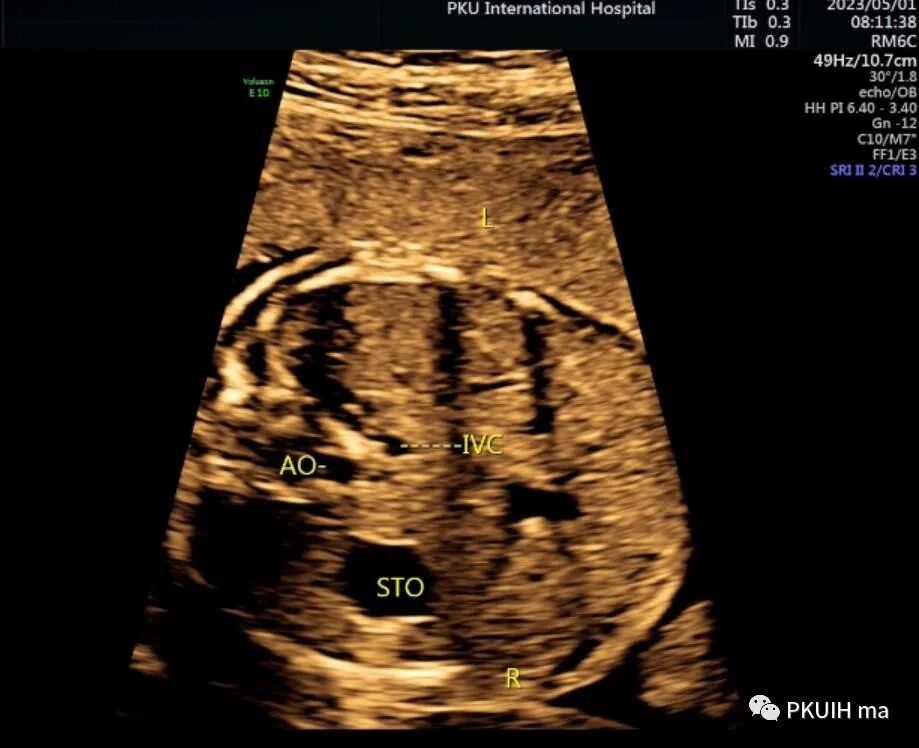

胎儿胃泡位于右侧,肝脏和胆囊位于左侧,主动脉位于脊柱右前方,下腔静脉位于脊柱左前方